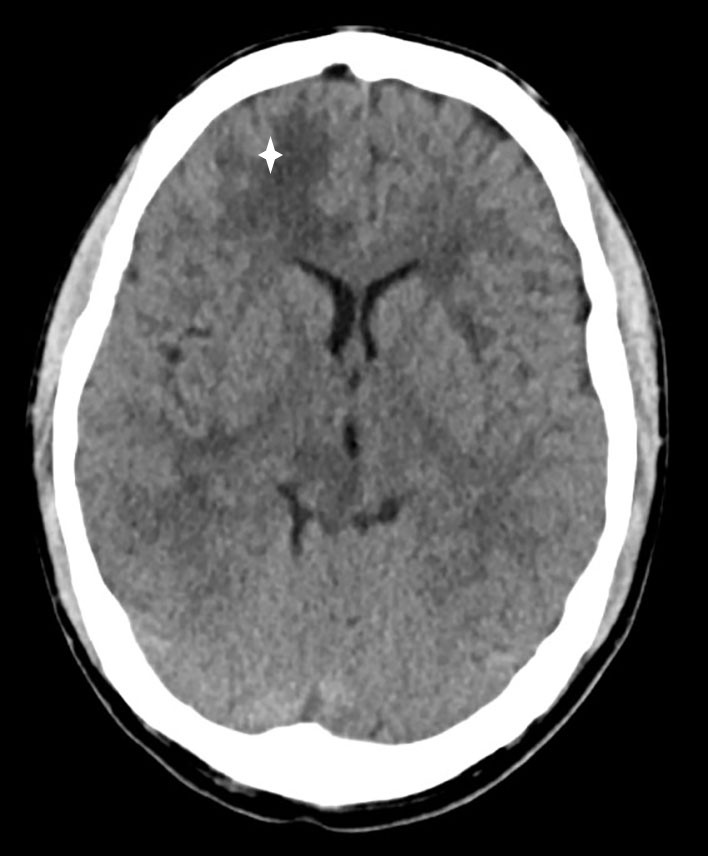

CT-undersøkelse uten kontrast av hodet ble tatt umiddelbart etter innleggelse og viste lavattenuerende forandringer i hvit substans frontalt i høyre storhjernehemisfære (fig 1) og i høyre lillehjernehemisfære. Supplerende magnetisk resonanstomografi av hjerne og medulla påfølgende dag avdekket multiple lesjoner i hjernestamme, lillehjerne og begge storhjernehemisfærer (fig 2). Nevroradiolog vurderte funn som forenlig med multiple metastaser, hjernetuberkulose, parasittsykdom eller septiske embolier med sekundær abscessdanninger. Spinalvæskeundersøkelse viste leukocyttnivå på 9 · 109/l, men ellers normale verdier for erytrocytter, glukose og protein. Det ble samme kveld utført CT av thorax, abdomen og bekken for å se etter tegn til ekstracerebral sykdom, inkludert kreft, bakterielt infeksjonsfokus, tuberkulose i eller utenfor lunger, eventuelt tegn til parasittsykdom. Denne avdekket multiple mikronoduli i lungene, mest i apikale deler av begge overlappene, én litt større nodulus apikalt og lateralt i venstre overlapp samt en liten høyattenuerende lesjon til høyre for avgangen av høyre hovedbronkus som var forenlig med en forkalket lymfeknute (fig 3). Det var multiple lavattenuerende lesjoner i abdomen og bekken, mest i øvre del av lever, og i tillegg lesjoner i nyre og prostata. Radiologen beskrev funnene som mest forenlig med miliær tuberkulose.